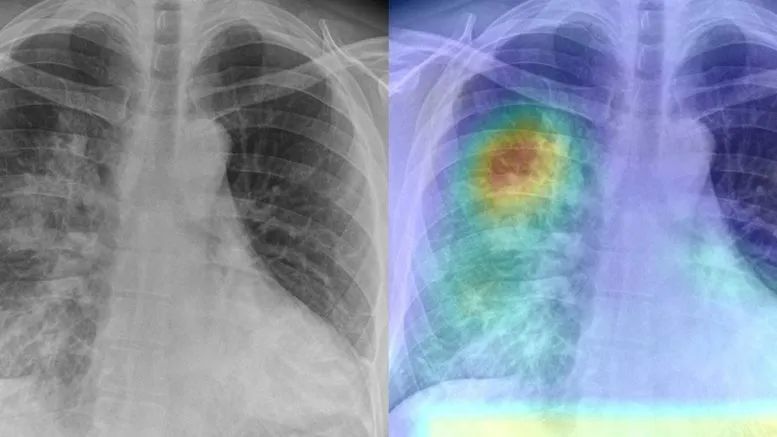

近年来,人工智能在处理医学影像方面取得了实质性的进展,但新冠疫情大爆发期间,似乎出现了这样一种危险的趋势:一些人仓促地使用存在瑕疵的、有问题的数据来训练针对 COVID-19 的人工智能解决方案,这一做法不仅对患者和医生没有任何帮助,而且还会损害人工智能的声誉。

而一些研究人员已经开始收集和创建自己的数据集,为未来的任务做准备。从网上搜集来的 X 光照片和 CT 图像似乎随处可见,而且随着创作者不断添加图像,网上这些图像也在不断增加。

由于这类数据的可获得性,以及基础人工智能知识和工具存在的普遍性,许多人工智能爱好者和初创公司已经冲动地开始研发从 X 光照片中检测 COVID-19 的解决方案。

有些网站和博客甚至提供了关于如何从 X 射线扫描中高精度地检测出 COVID-19 的建议,还有一些人给出了从 X 光照片中检测 COVID-19 的教程。

甚至还有一些未经同行评议的论文,更进一步,用 “COVID-Net” 这样的夸张名字为他们的解决方案进行 “洗礼”。这种类型的工作通常缺乏许多实验细节,来解释如何通过极少数患者的医学影像图像满足深度神经网络的需求。

这类论文往往未经证实,也未经放射科医生的实验指导,甚至在数据集的创建者还没来得及对其收集数据的过程进行足够解释的情况下,这些研究就匆匆公之于众了。

为了克服数据量小的问题,AI 爱好者和初创公司将他们拥有的为数不多的 COVID-19 图像与其他类似肺炎数据集这样的公共数据集混合在一起。这是一个很聪明的做法,但也会产生一些麻烦的后果,比如 COVID-Nets 会将一到五岁的小儿肺炎当成新冠病例,与成人 COVID-19 患者进行比较。